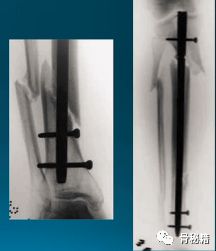

很有可能,你的髓内钉植入近端1/3的时候是这样……

近端1/3骨折,尤其是前后斜行的骨折线时,你插入髓内钉以后,经常会形成近端后倒。

看下面的病例,胫骨干中部比较稳定,而远端则形成了摆动效应,十分不稳定,就是传说中的“筷子搅大缸”

轻微粉碎的病例,多发伤患者,皮肤条件不好,不敢切开,先植入两枚阻挡钉,后方一个,侧方一个,进针之后,发现导针穿出后方……

说明这后方的阻挡钉没设计好,然后又在下方植入了一个阻挡克氏针

一个多阶段的胫骨骨折,看着移位不大

植入髓内钉后……

这样的骨折肯定长不上了,病人看了估计都会天天找你吧?翻修,近端加阻挡钉,小钢板